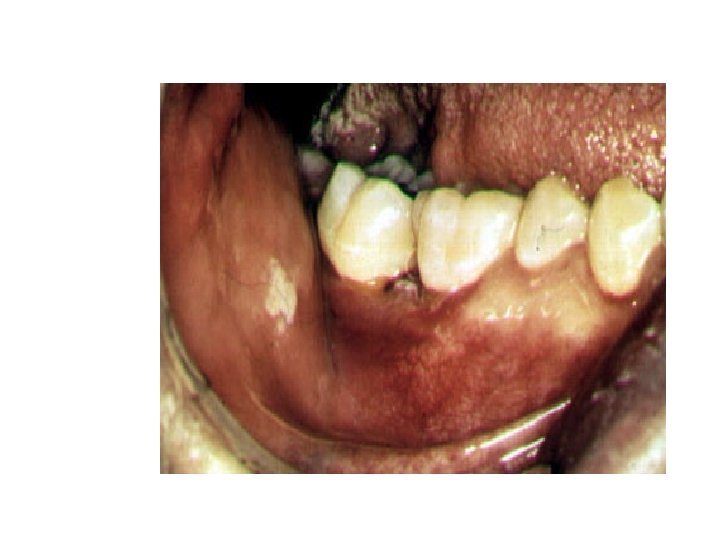

HISTOPLASMOSIS (Histoplasma capsulatum) Histoplasmosis is a systemic disease, mostly of the reticuloendothelial system, manifesting itself in the bone marrow, lungs, liver, and the spleen. In fact, hepatosplenomegaly is the primary sign in children, while in adults, histoplasmosis more commonly appears as pulmonary disease. This is one of the most common fungal infections. The ecological niche of H. capsulatum is in blackbird roosts, chicken houses and bat guano. Typically, a patient will have spread chicken manure around his garden and 3 weeks later will develop pulmonary infection. Histoplasmosis is a significant occupational disease in bat caves in Mexico when workers harvest the guano for fertilizer. In the endemic area the majority of patients who develop histoplasmosis (95%) are asymptomatic. The diagnosis is made from their history, serologic testing or skin test.

In the patients who are clinically ill, histoplasmosis generally occurs in one of three forms: acute pulmonary, chronic pulmonary or disseminated. There is generally complete recovery from the acute pulmonary form (another "flu-like" illness). However, if untreated, the disseminated form of disease is usually fatal. Patients will first notice shortness of breath and a cough which becomes productive. The sputum may be purulent or bloody. Patients will become anorexic and lose weight. They have night sweats. This again sounds like tuberculosis, and the lung X- ray also looks like tuberculosis, but today radiologists can distinguish between these diseases on the chest film (histoplasmosis usually appears as bilateral interstitial infiltrates. (The skin test is NOT used for diagnostic purposes, because it interferes with serological tests. Skin tests are used for epidemiological surveys.